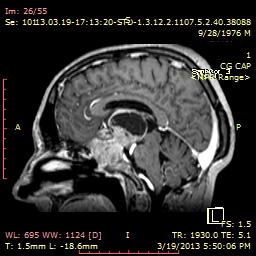

De aproximativ doi ani, vederea lui Cornel este din ce în ce mai afectată. Controlul imagistic RMN efectuat în 2013 a decelat o tumoră de dimensiuni mari, de aproximativ 8 cm, care este aderentă la structurile nervoase din vecinătate, cu distrugerea aproape completă a glandei hipofize şi afectarea importantă a nervilor optici.

Imagini ale tumorii au fost proiectate pe un monitor TV în sala de operatie cu ajutorul unui sistem computerizat de navigaţie 3D, functionând ca un GPS care în care in loc de hărţi avea imaginile RMN-ul pacientului. Această tehnologie modernă a permis neurochirurgului să verifice cu exactitate unde se află diverse structuri nervoase vitale în raport cu tumora. Nervii optici foarte deformati, cu o funcţionare la limită, au fost manipulaţi foarte delicat, pentru a preveni pierderea definitivă a vederii.